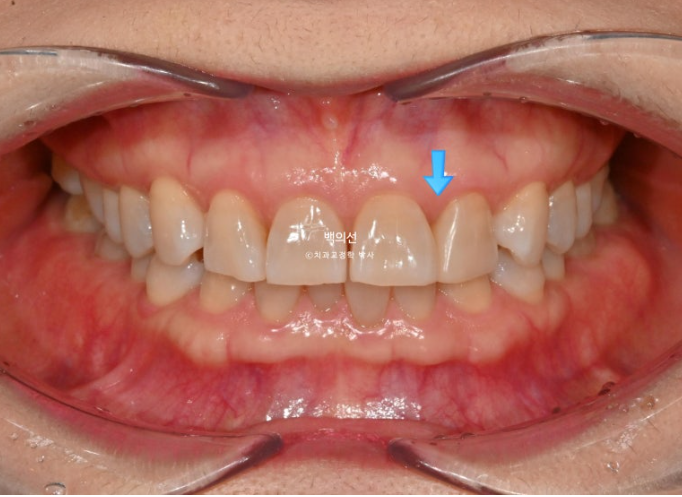

파란 화살표는 벌어진 틈을 레진으로 메꿔놓은 곳 입니다.

25.02

레진 치료를 감쪽같이 잘 해놓으셨습니다.

파란 화살표는 틈을 메워놓은 레진 입니다.